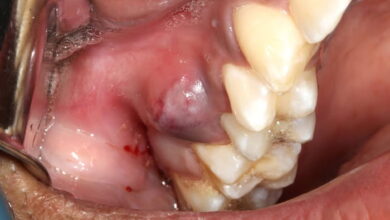

آیا کامپوزیت دندان برای افرادی که مشکلات لثه دارند مناسب است؟

کامپوزیت دندان برای افراد با مشکلات لثه: راهنمای جامع انجام کامپوزیت دندان برای افرادی که با مشکلات لثه، از جمله التهاب (ژنژیویت) یا بیماریهای پیشرفتهتر (پریودنتیت)، دست و پنجه نرم میکنند، یک اقدام پرریسک و عموماً غیرقابل توصیه است. سلامت لثه به عنوان فونداسیون و بستر اصلی دندانها، یک پیشنیاز قطعی برای موفقیت هرگونه درمان زیبایی، از جمله کامپوزیت، محسوب…